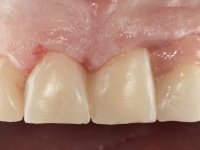

Paciente do sexo feminino, com 47 anos não fumadora. Apresentou-se na consulta com o dente 1.3 com tratamento endodôntico e com um espigão falso coto fundido, reabilitado com uma coroa provisória. Os dois incisivos laterais superiores são conoides e de reduzida dimensão. O dente 2.2 apresenta mobilidade, consentânea com uma significativa reabsorção óssea entre o dente 2.1 e o dente 2.3 Os dois incisivos centrais estão separados por um diastema de 3mm e o dente 2.3 apresenta uma oclusão cruzada com o dente antagonista. Verifica-se também a ausência de alguns dentes posteriores e uma higiene oral razoável. Na segunda intervenção realizada passados 8 anos, verificou-se que os incisivos centrais superiores se apresentavam cromaticamente mais escuros e apresentavam um sulco longitudinal no esmalte que estando pigmentado comprometia esteticamente o sorriso. O trabalho realizado na primeira fase do tratamento mostrava-se competente estética e funcionalmente. Por fim, um ano após a última intervenção, a paciente apresentou-se com uma fratura da faceta colocada no dente 2.1 provavelmente em resultado de estar em contacto com o coto do implante. A rigidez da anquilose implantar, pode ter sido a causa desta fratura. Outros casos deste tipo de fratura já foram observados por mim em situações clínicas idênticas. A faceta do dente 1.2 apresentava-se esteticamente comprometida e a própria estrutura dentária apresentava uma pequena cárie e, pelo que se recomendaria a sua substituição.

O tratamento iniciou-se com a re -preparação do coto do espigão falso coto fundido, com o objetivo de colocar as linhas de acabamento cervical com uma localização intra-sulcular e simultaneamente confecionar uma coroa provisória adaptada. Com um tratamento ortodôntico muito simples, fechou-se o diastema entre os incisivos centrais superiores e estabilizou-se esta posição com um arame colocado na superfície palatina dos centrais, funcionando como contenção. Posteriormente procurou-se fazer uma tração ortodôntica lenta do dente 2.2 com o intuito de diminuir, ainda que muito ligeiramente a perda óssea vertical nessa zona. Finalizada a tração, foi feita a extração do dente 2.2 e a zona foi reabilitada provisoriamente com uma coroa de resina composta colada aos dentes adjacentes. Foi colocado um implante dentário na zona do dente 2.2 sendo novamente colada a coroa provisória em resina, reabilitando provisoriamente a paciente durante o período de osseointegração. No dente 1.3 foi feita uma gengivectomia com bisturi elétrico, com a intenção de subir o nível cervical do 1.3 conseguindo uma maior harmonia com o dente 2.3. Estabilizados os tecidos moles, foi feita uma impressão com a técnica de moldeira aberta, utilizando silicones de adição de consistência “putty” e “light”. A recolha da cor, tanto da componente dentária como dos tecidos moles foi feita pelo ceramista no consultório.  No laboratório as impressões foram passadas a gesso e deram origem a modelos de trabalho que foram devidamente analisados. Foi decidido confecionar um “abutment” metalo-cerâmico aparafusado sobre o implante. Este “abutment” foi fundido com uma liga nobre e posteriormente revestido a cerâmica coronária e gengival. Dada a inclinação do implante o aparafusamento condicionou de forma inevitável a saída do orifício do parafuso pela superfície vestibular. No sentido de esconder esta situação, o desenho do “abutment” já foi idealizado com a intenção de acomodar na superfície vestibular a colagem de uma faceta feldspática. Este “abutment” foi provado em boca e foram feitos ajustes no componente cerâmico gengival. A sua adaptação aos tecidos moles foi feita tanto de forma subtrativa, com broca, como de forma aditiva, acrescentando resina composta de tonalidade gengival. Este acrescento de resina seria orientador do ceramista na colocação final da cerâmica de tonalidade gengival. A coroa que reabilitaria o dente 1.3 foi cimentada nesta consulta de prova com cimento de ionómero de vidro reforçado com resina composta. Finalizado o trabalho em laboratório da faceta sobre o 1.2 e o “abutment” e a faceta para o implante este foi colado em boca, após a colocação do isolamento absoluto. O trabalho satisfez plenamente a paciente. Durante oito anos a paciente foi seguida regularmente, mostrando-se agradada com o tratamento efetuado, no entanto começou a mostrar interesse em intervir esteticamente nos incisivos centrais superiores. Decidida a segunda fase da nossa intervenção, foi feita a preparação dentária dos dentes 1.1 e 2.1 para a colocação de duas facetas feldspáticas. Particular cuidado foi tido na preparação inter-proximal distal junto ao “abutment” do implante. Foi preciso avaliar muito pormenorizadamente o eixo de inserção da faceta em relação ao “abutment”. As facetas feldspáticas foram confecionadas em laboratório e posteriormente coladas em boca após a colocação de isolamento absoluto. Um ano após, iniciamos a nossa terceira fase de tratamento, após a faceta colada no dente 2.1 ter fraturado. A preparação dentária foi feita sobre a faceta colada, procurando estender mais para palatino o interface inter-proximal distal. O objetivo seria passar para mais palatino do ponto de contacto o interface faceta-dente. O preparo dentário do dente 1.2 também foi muito reduzido, limitando-se a criar um eixo de inserção. Após confecionadas a coroa total e a faceta em laboratório foram coladas em boca. Primeiro foi colada a coroa utilizando-se um isolamento relativo com teflon, posteriormente foi colada a faceta após a colocação do isolamento absoluto. Na coroa utilizei este tipo de isolamento para evitar a utilização de grampos. Seria difícil de aplicar pela forma e dimensão do dente e agressivo para os tecidos moles. Após a colagem foi avaliada a integração oclusal do trabalho.